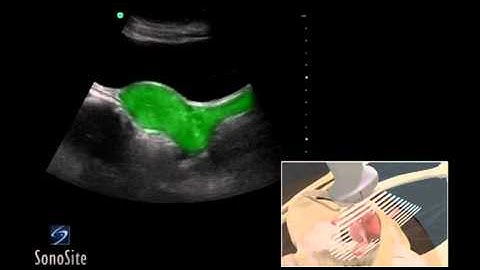

How to assess the pelvic hiatal area using a new 3D ultrasound technique